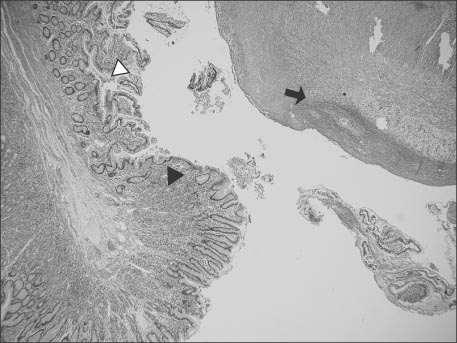

We immediately conducted abdominal X-ray and gastrointestinal ultrasonography for rule out of intussusception. But, there was no evidence of intussusception or appendicitis on gastrointestinal ultrasonography, with small amounts of fluid collection around small and large bowel (Fig. 1).

Fig. 1

Gastrointestinal ultrasonographic images show normal range of appendix intact (diameter 0.5 cm) (A) and intact ileocecal valve (B).

Fig. 1 Gastrointestinal ultrasonographic images show normal range of appendix intact (diameter 0.5 cm) (A) and intact ileocecal valve (B).